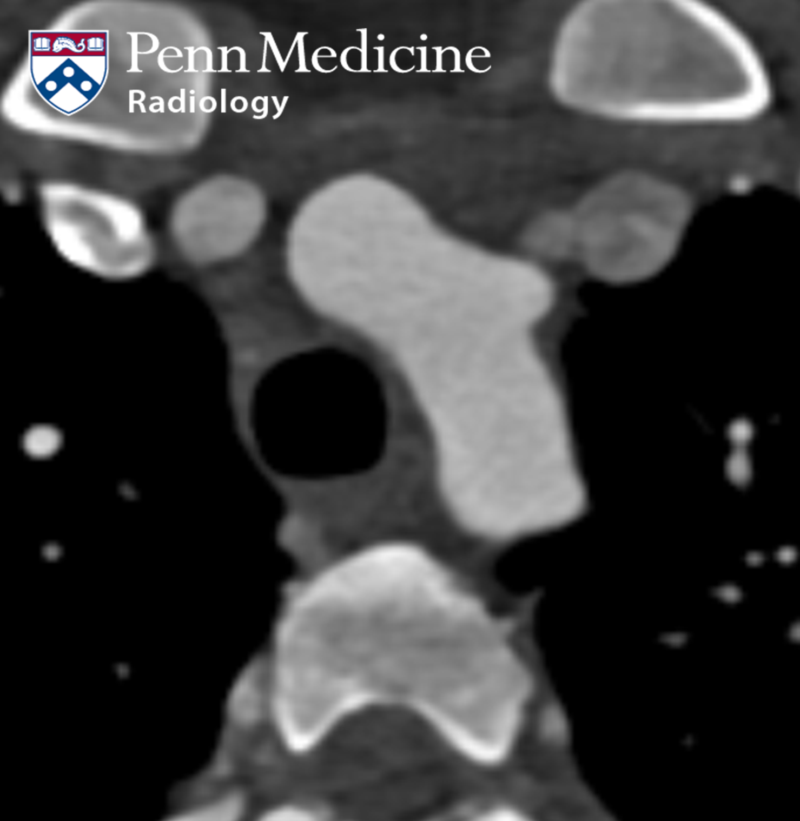

50-year-old man with progressive worsening dyspnea

Azfar Basunia

Open to access this content

Published Date: January 27, 2026

Tags:

Body

,

CT

PET

Thoracic

X-Ray